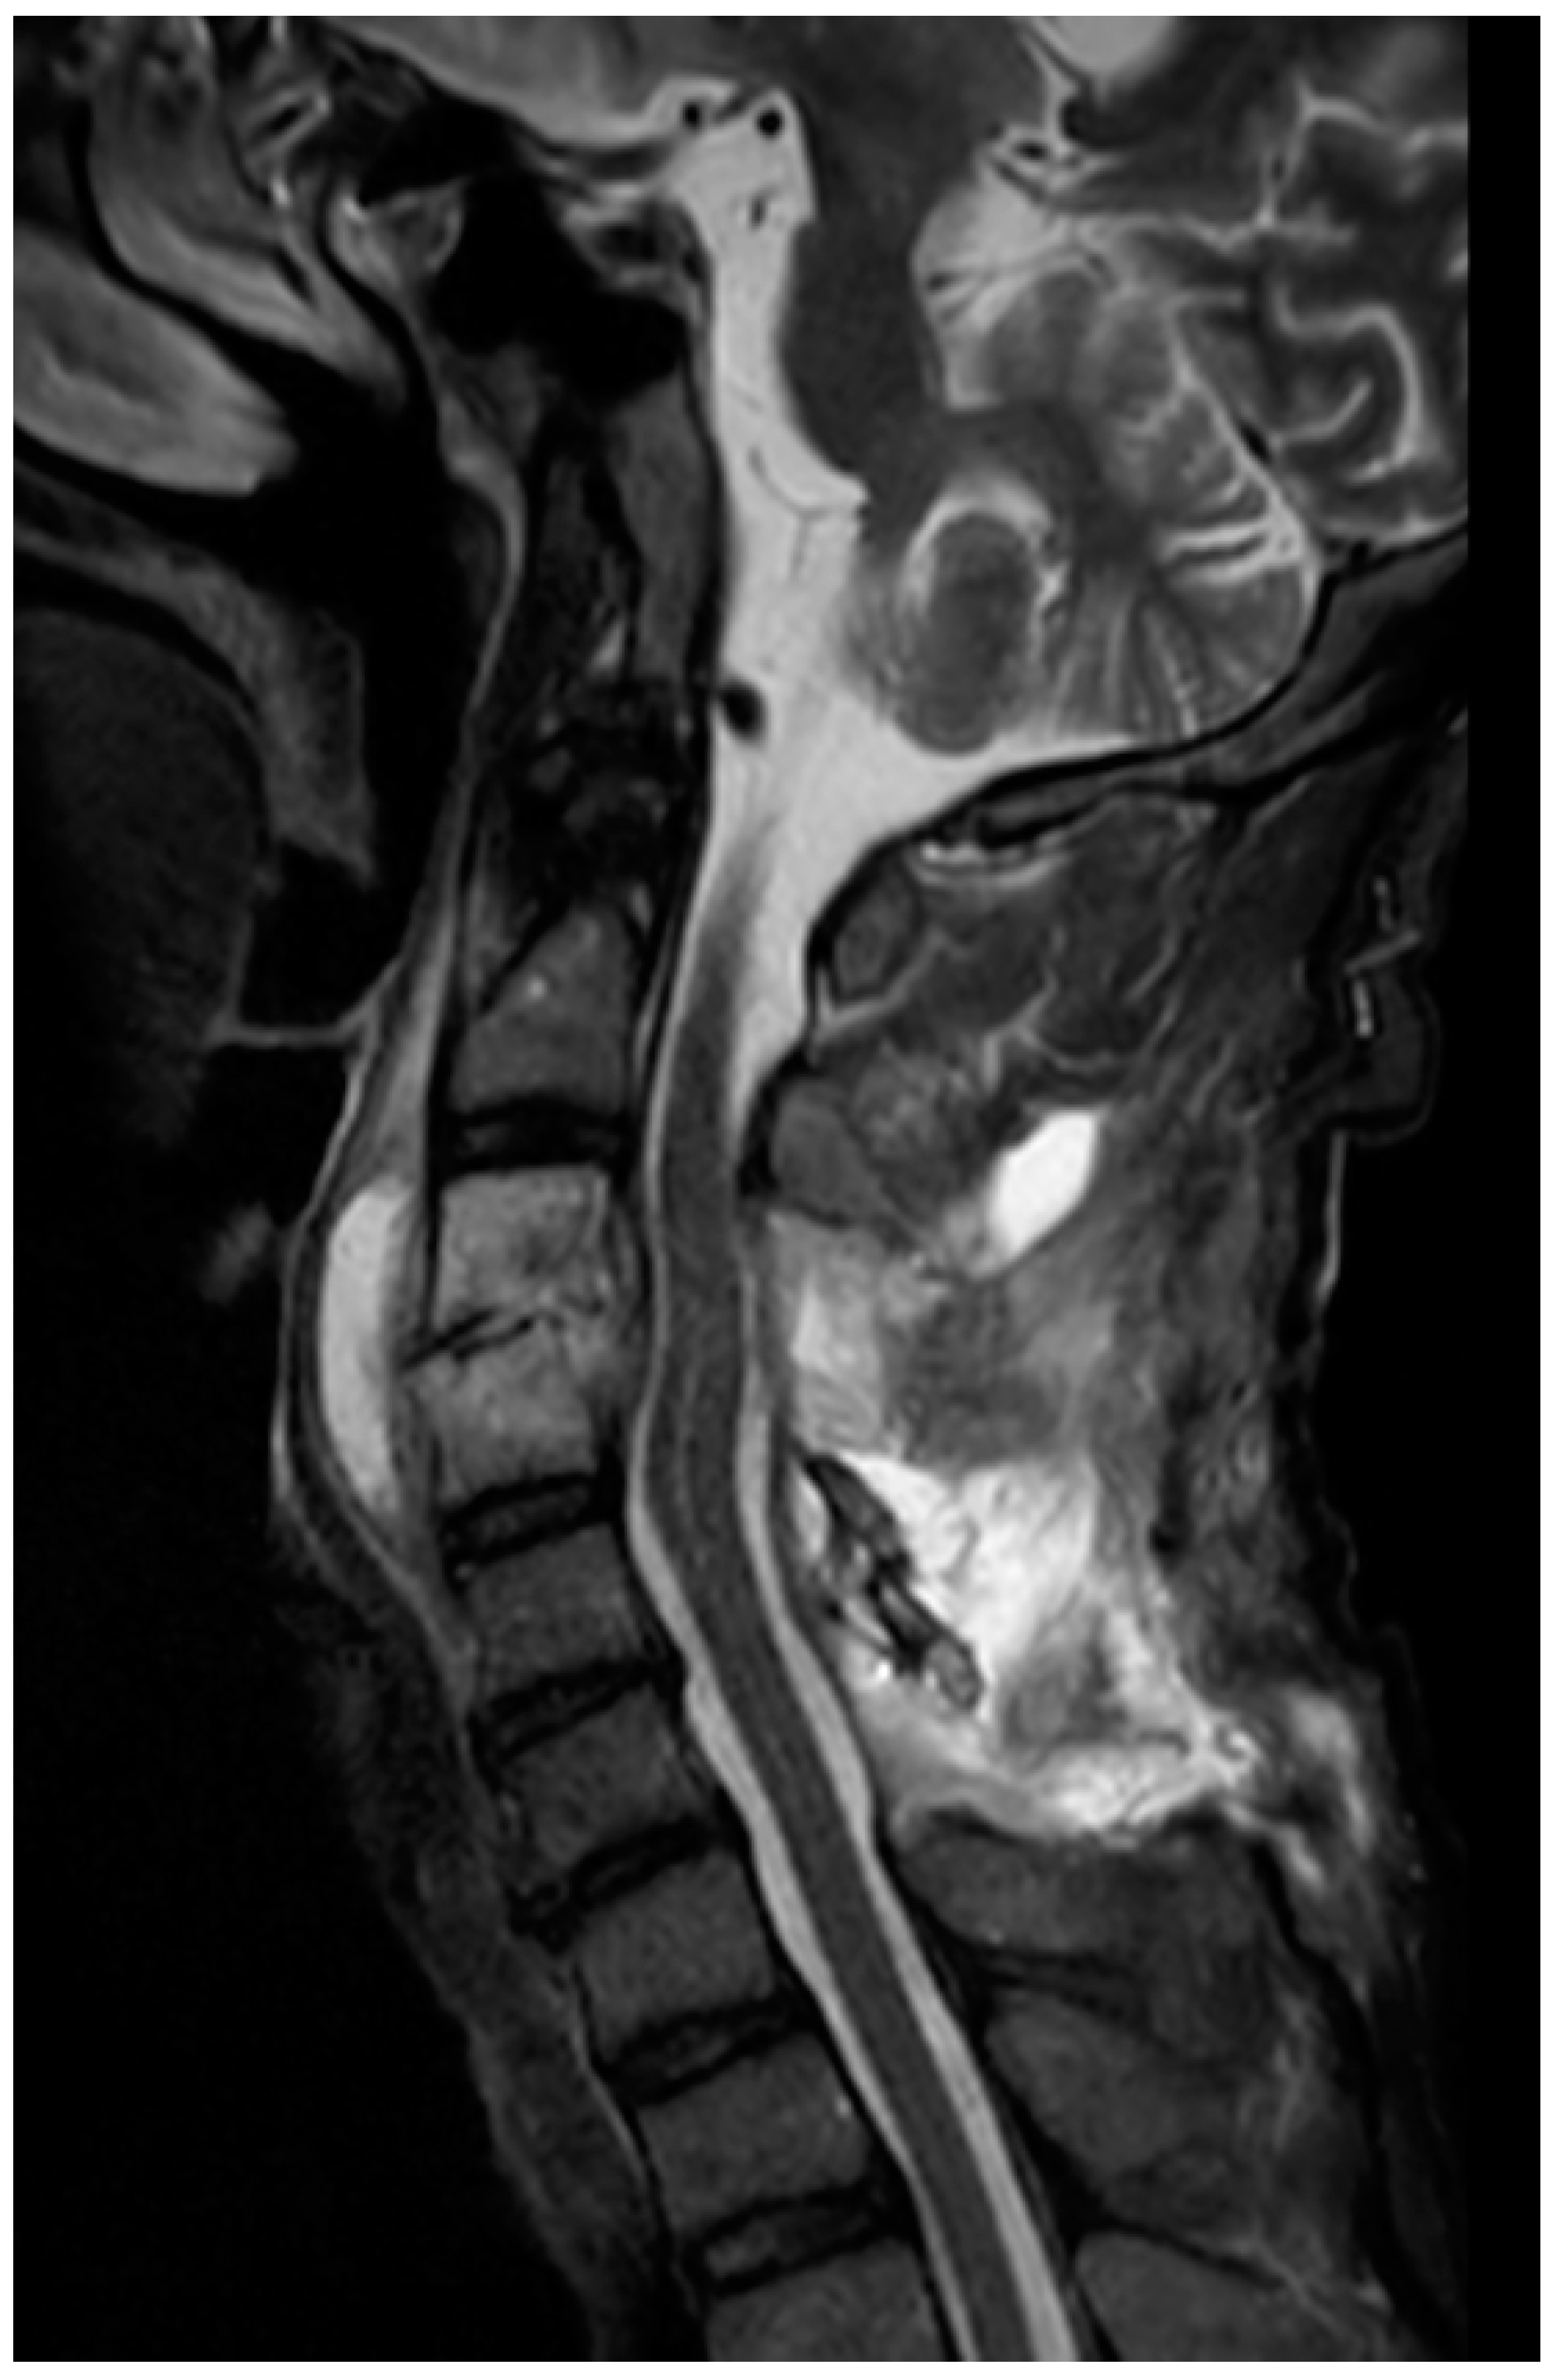

Laboratory data showed C reactive protein levels of 31.5 mg/dL and procalcitonin levels of 1.57 ng/mL with anemia and thrombocytopenia. Computed tomography (CT) and magnetic resonance imaging (MRI) of the cervical spine (Figure 1) revealed a C3 fracture with ventral and dorsal epidural space-occupying lesions compressing the cord.

Figure 1. MRI T2 STIR. Mid sagittal STIR MRI on admission (day 0) showing a dorsal epidural lesion at C3–C5 compressing the spinal cord; high signal with rim enhancement consistent with secondary infection of a post-traumatic hematoma.